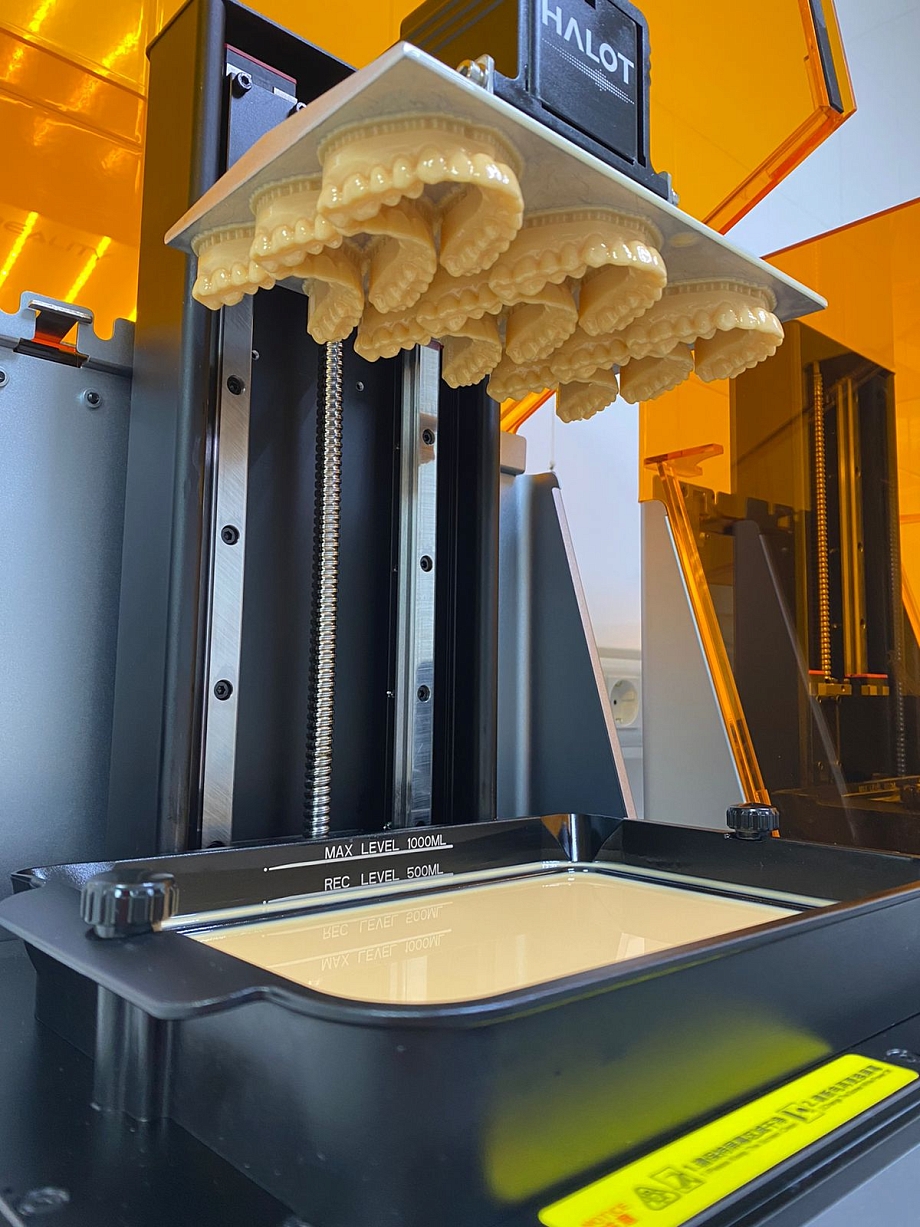

- Диагностика представляет собой несколько этапов. Диагностика состоит из статических и динамических методов исследования. Пациент сначала проходит статическую диагностику, которая включает: компьютерную томографию и теле рентгенографию позволяет определить состояние костных элементов височно-нижнечелюстного сустава и степень разрушения тканей и определить необходимые процедуры, цифровое сканирование зубов с использованием современных сканеров и фотографии позволяет получить точные данные зубных рядов для изготовления с помощью принтера 3Д моделей челюстей. К динамическим методам диагностирования относятся цифровая аксиография, которая с высокой точностью проводит запись движения ВНЧС при различных нагрузках и электромиографию, записывающую биопотенциал тонуса мышц при жевании.

- Мы разработали цифровую окклюзионную шину, она представляет собой съемное приспособление – незаметное и изготовленное из прозрачного материала. Изготавливают ее с помощью CAD/CAM технологии - это компьютерные программы для моделирования конструкции шины и высокоточное фрезерное пяти осное оборудования для изготовления внутриротового аппарата из современного медицинского полимера. В свое время мы проводили ряд исследований со всеми окклюзиоными шинами, которые присутствуют в стоматологическом мире. И цифровая окклюзионная шина нашего производства показала, что она в 2,5 раза эффективнее своих предшественников. Соответственно, использование этой шины помогает восстановить положение нижней челюсти в ту позицию, которая у пациента была утрачена.